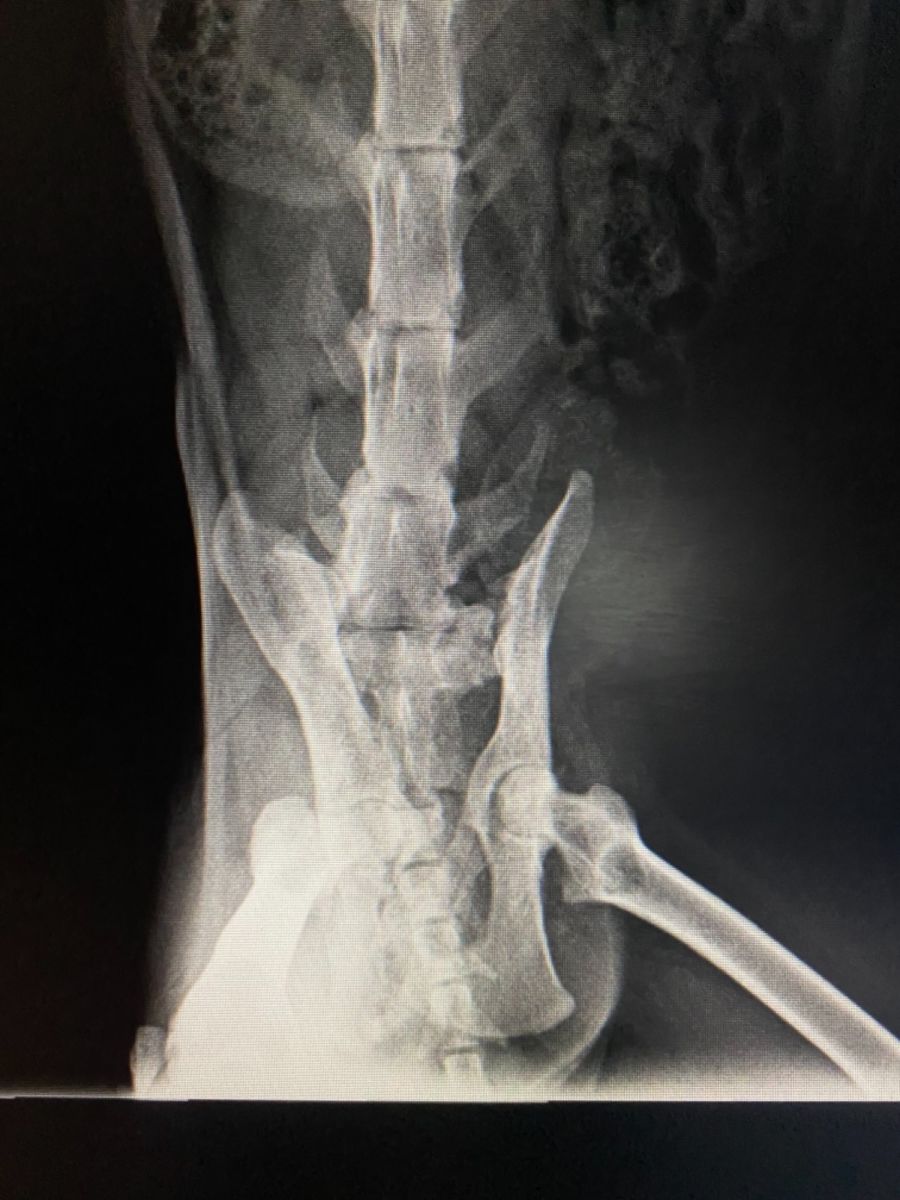

Jolene has a severe limp, stemming from the pelvis/hip, the leg is non weight bearing. Her veterinarian assures us she is not in any pain and I have never observed any indication of discomfort either.

Our veterinarian will be more that happy to discuss her condition with you, I’ve also added photos of her radiographs to the gallery.